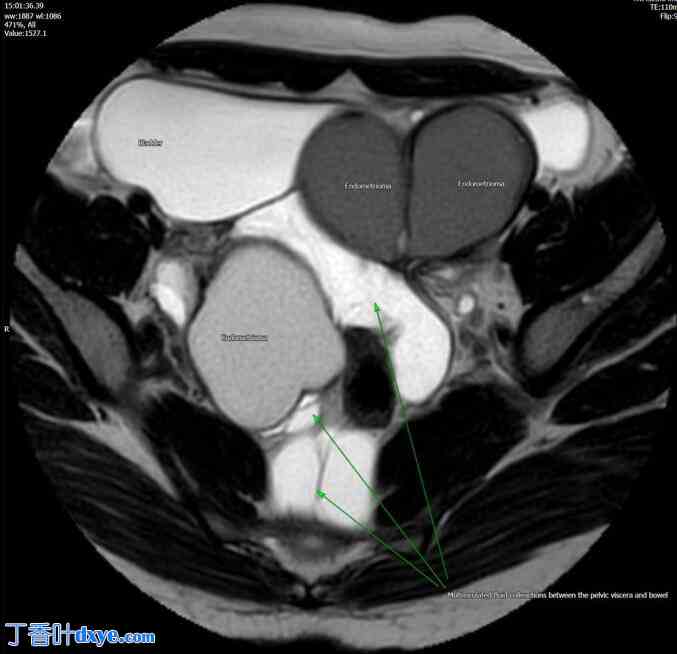

磁共振成像 (MRI) 显示盆腔内多发清晰的囊性结构、子宫腺肌病、双侧子宫内膜异位症以及子宫与直肠乙状结肠后连接处粘连(图1、图2)。由于影像学检查结果与子宫内膜异位症的诊断并不完全一致,因此进行了诊断性腹腔镜检查。

图 2.

经中部骨盆的 T2 轴位磁共振图像显示双侧子宫内膜异位瘤,其间可见多房积液,经组织学证实为间皮瘤。